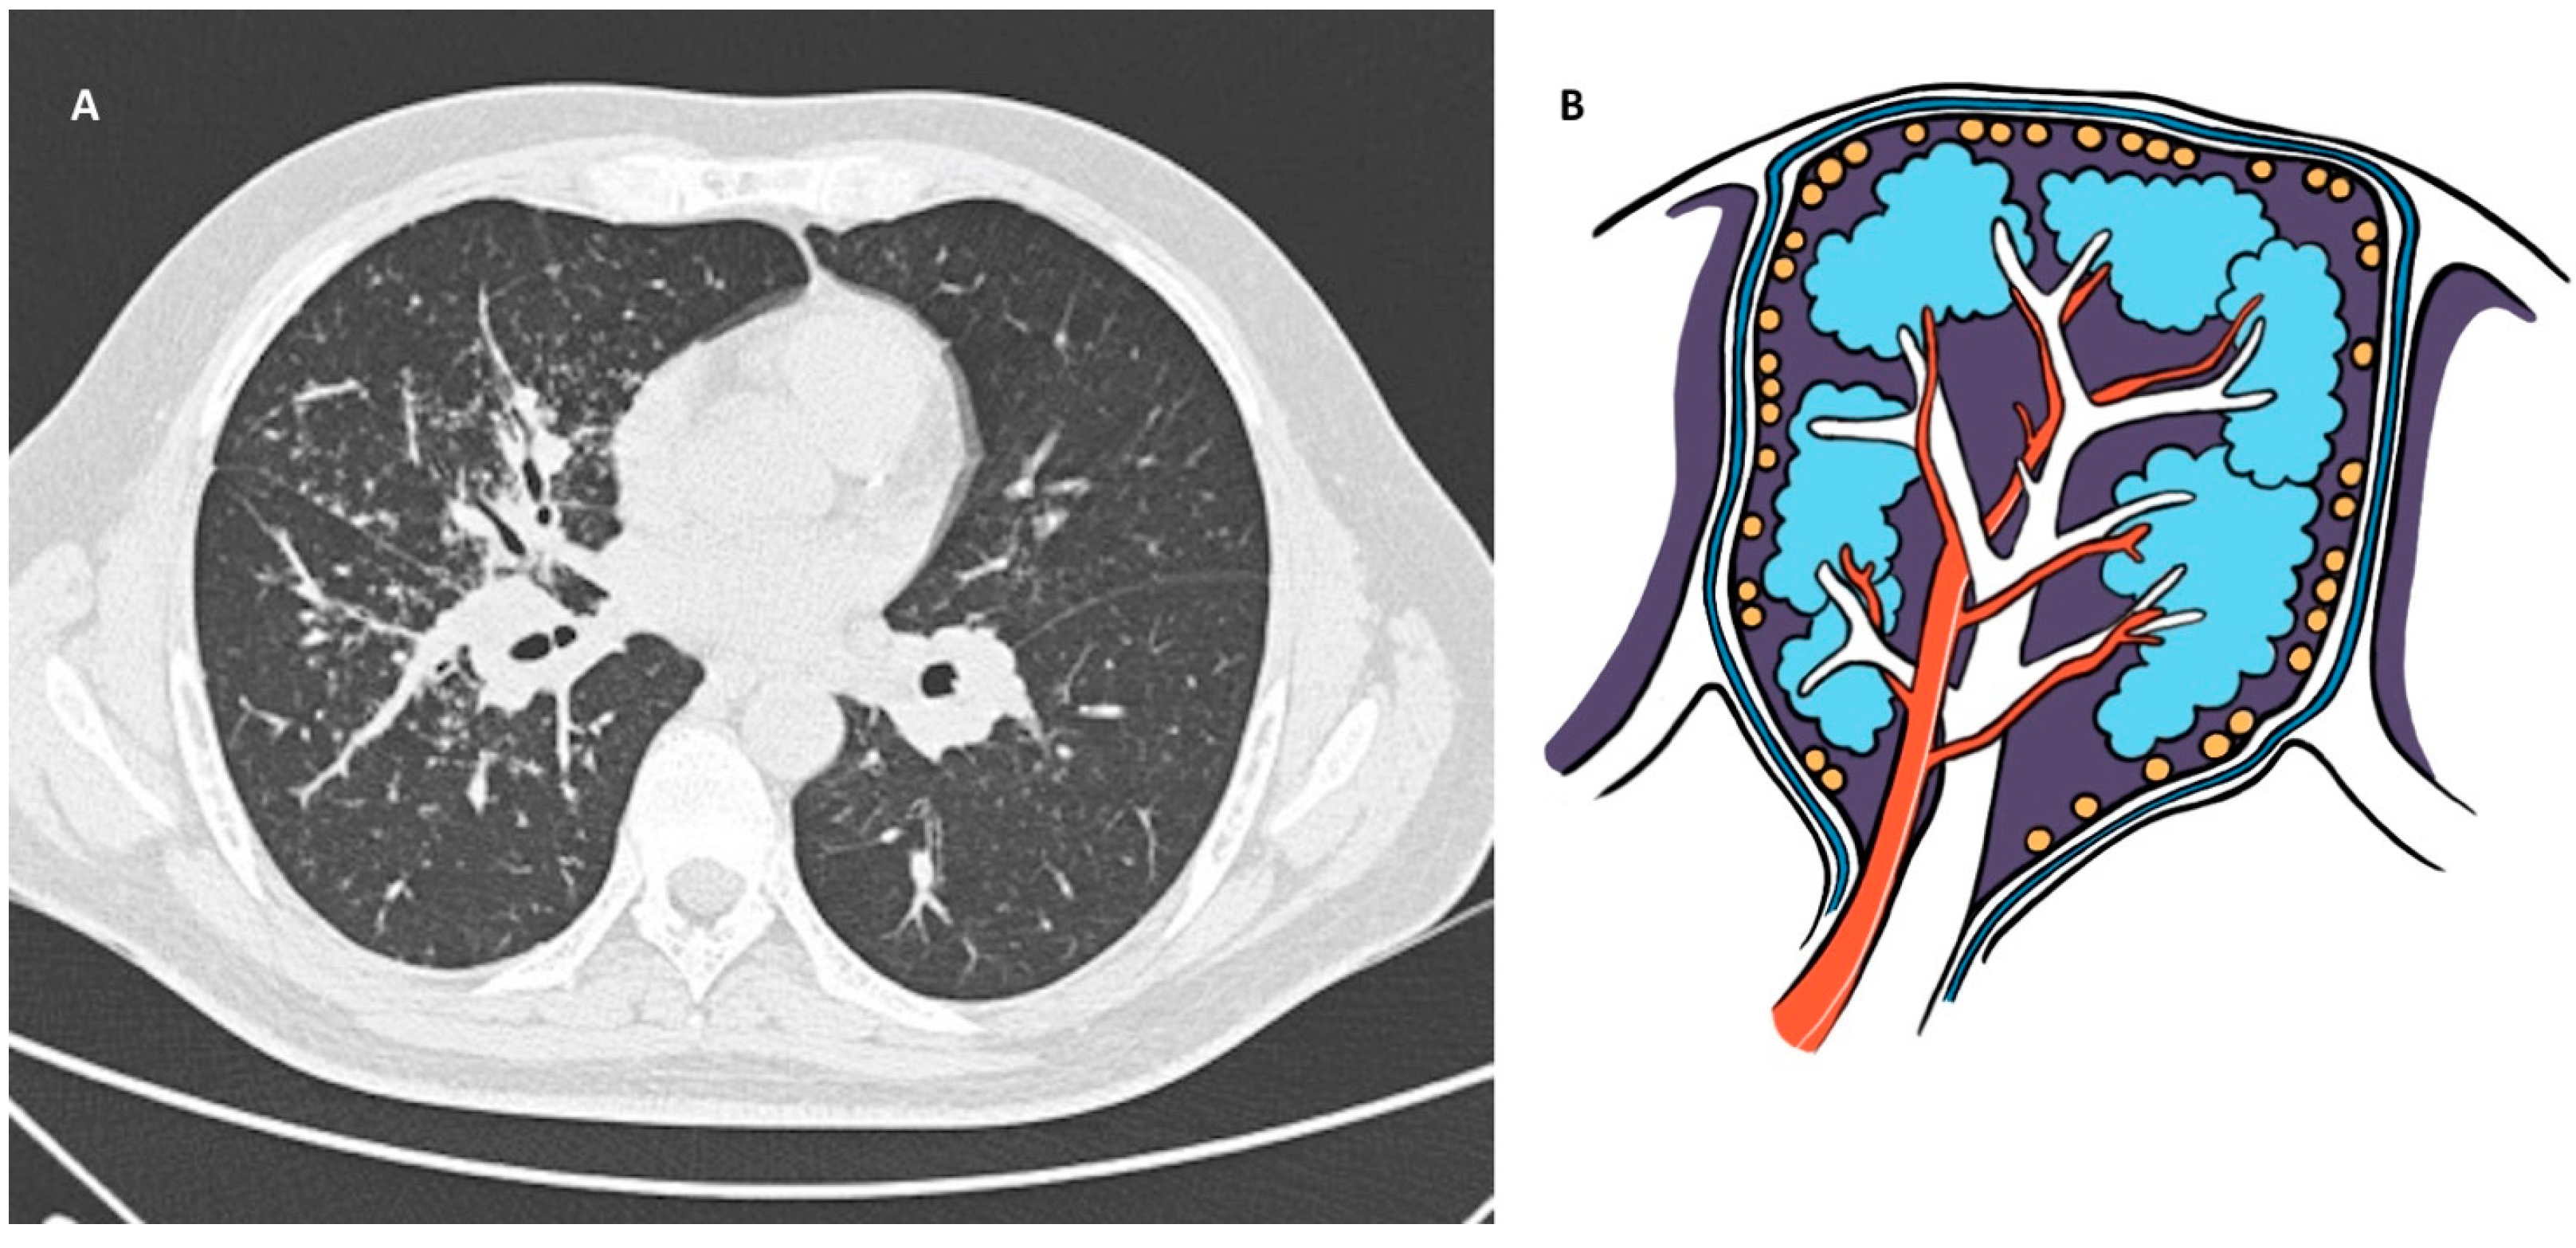

2. Sarcoidosis

2.4. Diagnosis